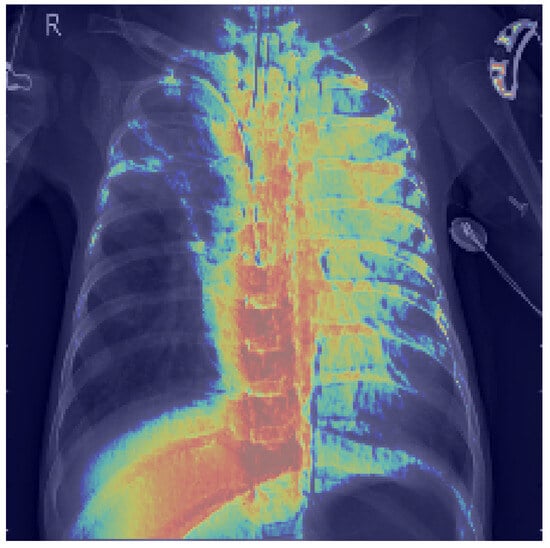

3.8. Explainability Analysis

- Selvaraju, R.R.; Cogswell, M.; Das, A.; Vedantam, R.; Parikh, D.; Batra, D. Grad-CAM: Visual Explanations from Deep Networks via Gradient-Based Localization. In Proceedings of the 2017 IEEE International Conference on Computer Vision (ICCV), Venice, Italy, 22–29 October 2017; IEEE: Piscataway, NJ, USA, 2017; pp. 618–626. [Google Scholar] [CrossRef]